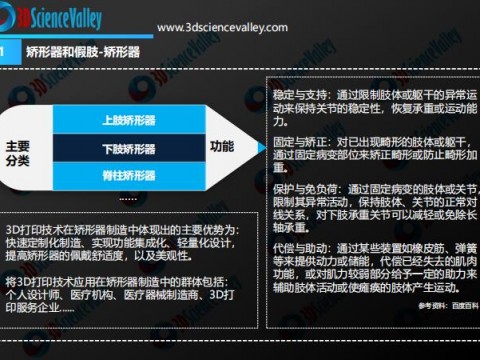

- 王金武教授团队研发3D打印矫形器,让膝关节炎病人不再担忧“人老腿先老”